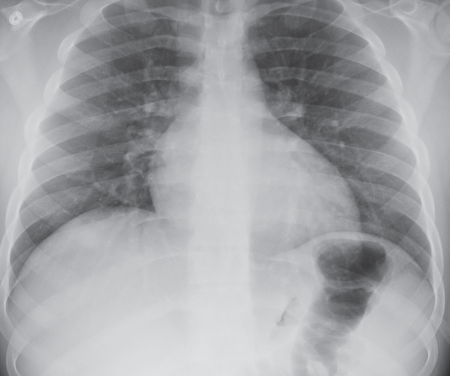

A 49-year-old male presented to the emergency room with hemoptysis, coughing up 400 cc of bright red blood.

A 71-year-old female with no significant past medical history presented to the hospital with sudden onset of massive hemoptysis.

A 46-year-old male presented with a history of intermittently increasing dyspnea on exertion over the past 3 years.